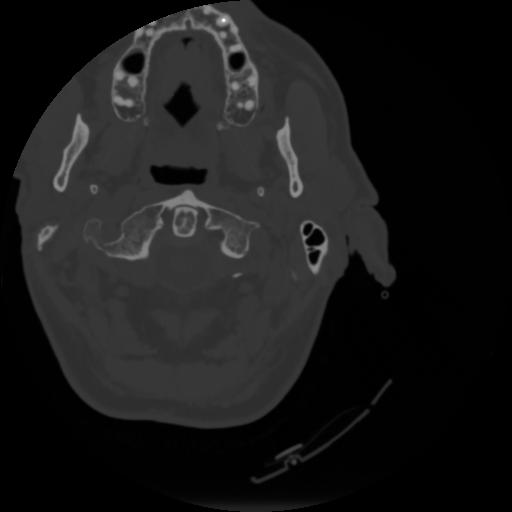

4 CEREBRO,,Vol,0.5,CEREBRO,,